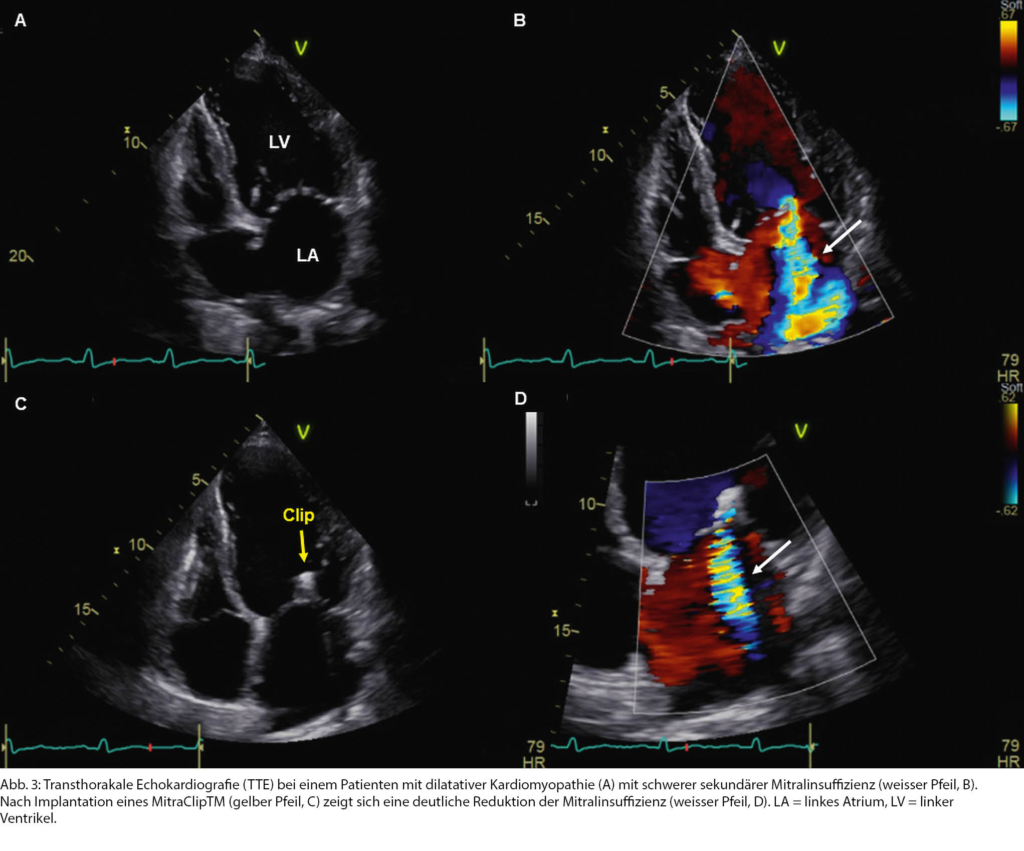

- Update valvuläre Herzkrankheiten: Entscheidungen im interdisziplinären Herzteam anhand von Beispielen